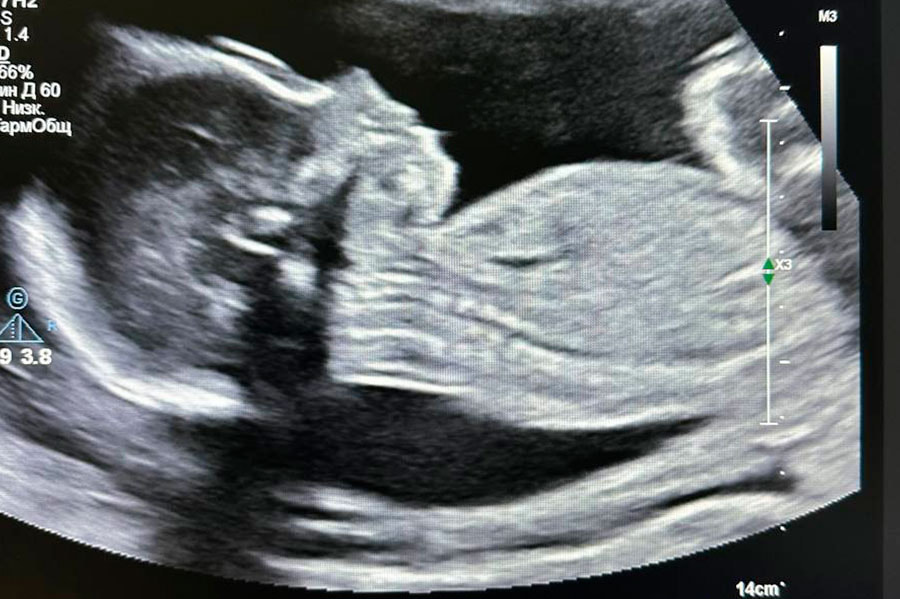

Ранее белорусские кардиохирурги впервые в истории страны провели операцию на сердце у женщины на 23-й неделе беременности.

Пациентке – 33 года. Врачи диагностировали у нее миксому левого предсердия – доброкачественную опухоль, которая несла прямую угрозу жизни. Операцию провели с применением искусственного кровообращения, что само по себе представляет серьезный риск – особенно во время беременности.

К вмешательству привлекли специалистов двух центров – РНПЦ “Кардиология” и РНПЦ “Мать и дитя”. Хирургам удалось сохранить и беременность, и здоровье женщины. Она доносила ребенка до 38 недель, и 2 октября родила мальчика весом 3230 граммов.

Роды прошли путем планового кесарева сечения. Состояние новорожденного – удовлетворительное, по шкале Апгар ребенок получил хорошие баллы.